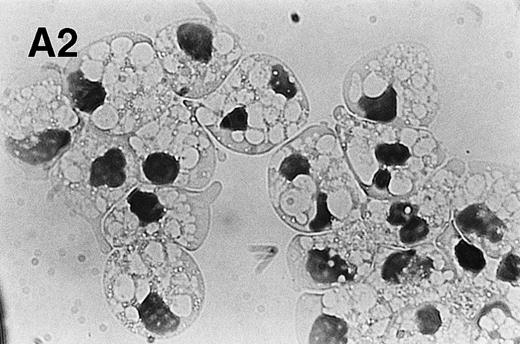

The protein kinase C activator, PMA, activates the NADPH oxidase in neutrophils, leading to a burst of reactive oxygen species similar to what is seen when neutrophils ingest invading pathogens.33,34 We found that PMA (200 nmol/L) rapidly induced morphologic changes, which were distinct from those observed in constitutive and Fas/APO-1–triggered apoptosis, with an increase in cell size and the appearance of numerous vacuoles throughout the cytoplasm (Fig 4A). Moreover, in agreement with a previous report by Takei et al,35 we were unable to detect any DNA fragmentation in PMA-treated cells (data not shown). However, PS exposure was evident at 3 hours and was markedly accelerated when compared with untreated neutrophils (untreated cells: 6.4 ± 3.1; PMA-treated cells: 38.5 ± 6.4; mean ± SD; n = 3; Fig 4B), demonstrating that changes similar to those observed in apoptotic cells are taking place.

PMA treatment of neutrophils results in rapid morphologic changes accompanied by externalization of PS. (A) Cytospin preparation of neutrophils cultured in medium alone (1) or treated for 3 hours with 200 nmol/L PMA (2). Note the presence of numerous vacuoles in the cytoplasm and the coalescence of the nuclear lobes after PMA treatment. Original magnification × 100. (B) PS exposure in unstimulated (panel 1) and PMA-treated (panel 2, 200 nmol/L) neutrophils after 3 hours of culture. PS exposure was determined by flow cytometric analysis of annexin V binding as described in Materials and Methods. The percentage PS exposure is indicated. PMA treatment also caused a marked increase in forward scatter of these cells, indicative of an increase in cell size (data not shown). Similar results were obtained with three independent donors.